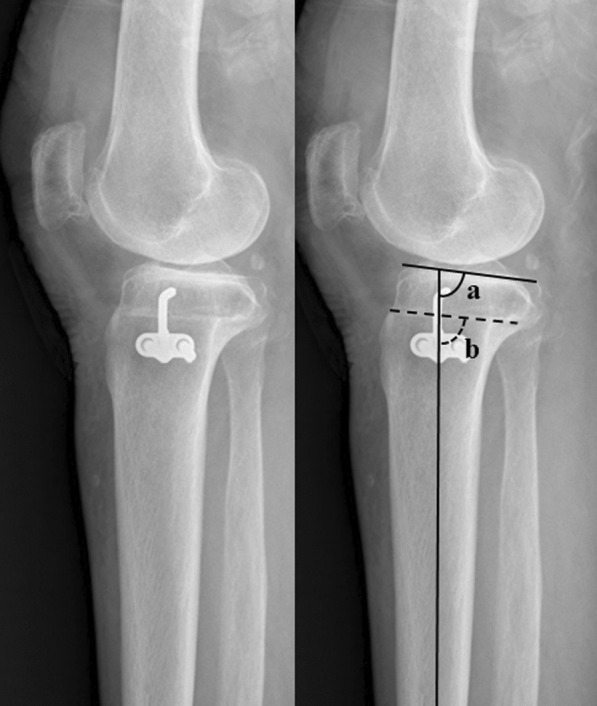

Methods: Each of the 50 conventional and CAS CW HTOs performed by single surgeon between 2015 and 2017 were included. The surgeon had experience of 140 cases of CAS CW HTOs before the study period. The groups were not different in terms of demographics. Clinically, the Western Ontario and McMaster Universities Osteoarthritis Index (WOMAC) and range of motion (ROM) were investigated. Radiographically, the mechanical axis (MA), change in posterior tibial slope angle (PTS), and parallel angle were evaluated. The proportions of inlier groups for the postoperative MA (within valgus 2° ± 3°), change in the PTS (within ± 3°), and parallel angle (< 3°) were compared.

Results: There were no significant differences in postoperative clinical results between the conventional and CAS groups. The MA was appropriately corrected in both groups (2.4° versus 2.9°, p = 0.317). The amount of change in PTS was significantly greater in the conventional group (-2.2° versus -0.8°, p = 0.018). The parallel angle was 5.3° in the conventional groups and 3.1° in the CAS group (p = 0.003). The proportion of inlier group was not significantly different in the postoperative MA (72% versus 78%) and change in the PTS (52% versus 66%). The proportion of inlier for the parallel angle was significantly lower in the conventional group (36% versus 60%, p = 0.027).